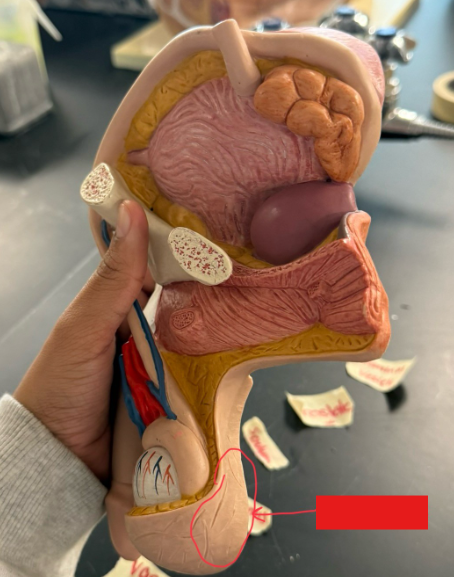

What is the name of the red box?

Ureter

What is the name of the red box?

Seminiferous tubules

Scrotum

What is the name of the brown box?

Testis